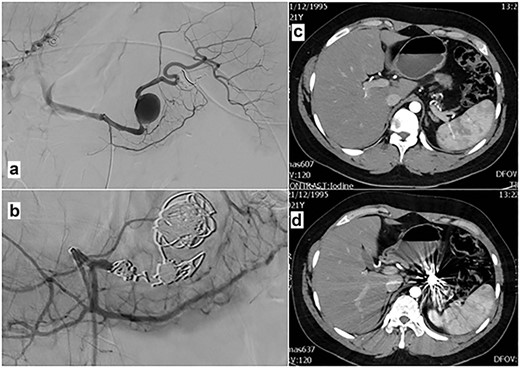

Thanks to the rather stable hemodynamic condition of the patient, and the fact that our institution is equipped to provide an endovascular approach, open surgery was excluded as the first therapeutic option; angiography with coil embolization of the aneurysm and proximal splenic artery was then performed. Under local anesthesia (injection of lidocaine solution 2%, Astra Zeneca, Athens, Greece), a percutaneous puncture of the right common femoral artery, and selective catheterization of the splenic artery was performed, using a 4-F Simmons 1 catheter (Cordis, Tipperary, Ireland). Subsequent angiography revealed the aneurysm, but an attempt to pass a microcatheter (Progreat®, Terumo, Leuven, Belgium) distally through the aneurysm failed. Embolization of the aneurysm itself and of the proximal splenic artery was decided, and 2D and 3D mechanically detachable fibered micro coils (Interlock-18, Boston Scientific, Cork, Ireland), and N-butyl-cyanoacrylate (NBCA) glue (Histoacryl®, Brown, Hessen, Germany) were used, preserving all of the collateral vessels for the spleen.

After embolization, the patient was stabilized and no signs of abdominal bleeding were observed on imaging. He was then transferred to our surgical department for further intense monitoring and treatment with intravenous fluids and blood transfusions. His recovery remained uneventful, as he did not develop further bleeding. He was discharged on the 12th day after the embolization in good condition; follow-up examination on an 8th-month basis showed preservation of the spleen, complete elimination of aneurysm and no other abnormal findings (Fig. 2).

Angiography after selective catheterization of the splenic artery (a) reveals the ruptured aneurysm. Angiography after the micro coil and glue embolization of the aneurysm and the proximal splenic artery (b) shows complete obstruction of the lumen. (c and d) Post contrast CT-images (arterial phase) 8 months after splenic artery aneurysm embolization, show complete elimination of aneurysm and preservation of the collateral arteries to the spleen.